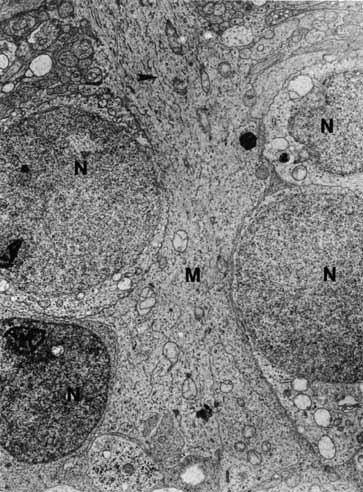

The photoreceptor outer segments have two important connections. One of these is to the inner segment, which is actually the cell body of the photoreceptor (see Fig. 21). The other connection is to the extracellular matrix that separates the photoreceptor outer segment from the pigment epithelial cell. Radioactive tracer experiments suggest that the sources of this extracellular matrix substance are the pigment epithelial and photoreceptor cells.99,100 The material, a glycoprotein consisting of chondroitin sulfate and sialic acid, is secreted into the space between the outer segments and the pigment epithelial cells by vesicles that originate in both cells. The function of this mucopolysaccharide-rich matrix is not well understood. It may provide a major route by which metabolites and nutrients pass between photoreceptor cells and their vascular supply. It may constitute the only intercellular bond between the outer segments of photoreceptors and the pigment epithelial cells, because there are no cellular connections such as tight junctions between these cells (see Fig. 23). Recent studies have identified interphotoreceptor retinol-binding protein as a major component of this matrix.100 This glycoprotein is believed to mediate the transport of a vitamin A derivative, retinol, between the photoreceptor and the pigment epithelium.

The connection of the outer to the inner segment of the photoreceptor is through a slender (0.2–0.3 μm in diameter) neck that is eccentric toward one side of the cell (see Fig. 21). The cilium, which is the embryonic basis for origin of the photoreceptors, is located in the neck and extends into the basal one third of the outer segment. It has nine pairs of microtubules. However, unlike motile cilia, the cilium has no microtubules centrally. The microtubules end in a modified centriole in the apex of the inner segment. The cilium functions as a conduit for metabolic materials going from the inner to the outer segments.

Inner Segments

The inner segment of the photoreceptor is the portion of the cell that metabolically services the outer segment. Whereas the outer segment shows high differentiation, containing only equipment necessary for the photoreceptor process, the inner segment possesses the cellular machinery essential for the metabolic and synthetic functions of the cell. There are two distinct morphologic regions in the inner segment, the ellipsoid and the myoid. The most prominent feature of the outer portion, or ellipsoid, of the inner segment is the abundance of large mitochondria at the apex (see Fig. 21). The ellipsoid appears to be more sensitive to anoxia than any other part of the photoreceptor cell.101 The staining characteristics of this area vary with the state of metabolic activity of the photoreceptor cell and may account for the subtle staining differences seen in the various types of photoreceptor cells. The mitochondria in the ellipsoid are compactly arranged. They are present in higher concentration in retinas with poor vasculature. In addition, the cones have a higher concentration and greater absolute number of mitochondria than the rods. There may be up to 600 mitochondria per cone.87 These mitochondria contain the normal enzymes for oxidative production of energy.102

The cilium or basal body arises from one of a pair of centrioles at right angles to one another in the distal portion of the ellipsoid. From the basal body originates the cross-striated fibril system of rootlets that course through the inner segment (see Fig. 21). The ciliary rootlets are composed of bundles of several hundred fibrils with a periodic alternation of light and dark zones 45 nm wide. They may extend as far as the nucleus of the cell. Their function remains speculative, although histochemical evidence suggests that they may play a role in energy or even in signal conduction. The energy-related enzyme, ATPase, has been found in the fibrils of these rootlets.103

The major protein synthetic activity and assembling of synthetic products in the inner segment take place at its proximal portion, or “myoid,” which houses the rough endoplasmic reticulum, ribosomes, and large Golgi complex associated with numerous vesicles. Because this region may be the source of the acid mucopolysaccharide in the extracellular space between the photoreceptor outer segments, disturbances of this synthetic or assembling facility could result in weakening of the normal retina-pigment epithelium adhesion. Such a defect could make this union more delicate and subject to separation in the presence of a retinal tear or exudative process originating from either the retina or the choroid.

Outer Nuclear Layer